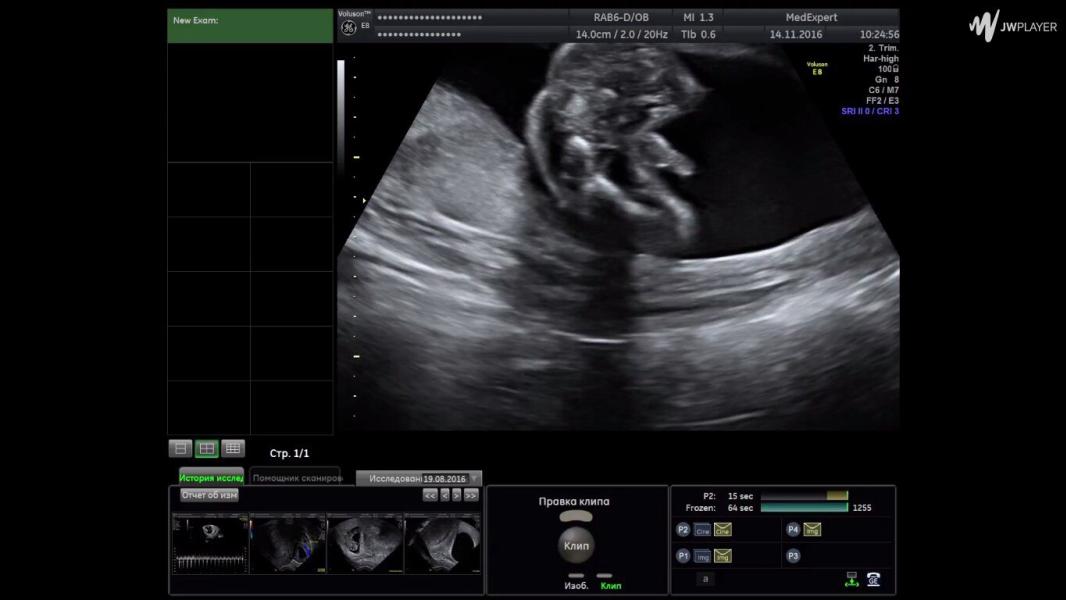

Когда ты- мужчина! И гордо доказываешь это уже на УЗИ))👼🏼🔞 и так было каждый раз, ни одной фотки с лицом)

@i.mahorkina, я чёт стручок приблизительно разглядела, а срок это какой по УЗИ?

@amsims1, и у нас вот) лицо двумя руками закрывал или отворачивался) зато пипиську- смотрите сколько угодно, во вам😀👍🏼

Да да и у нас так же было. Только поднесли датчик и вот оно! Все прелести выставил. Лицо ни разу не показал

И у нас так было 😂 лицо прятал, а писюн всегда показывал 😀